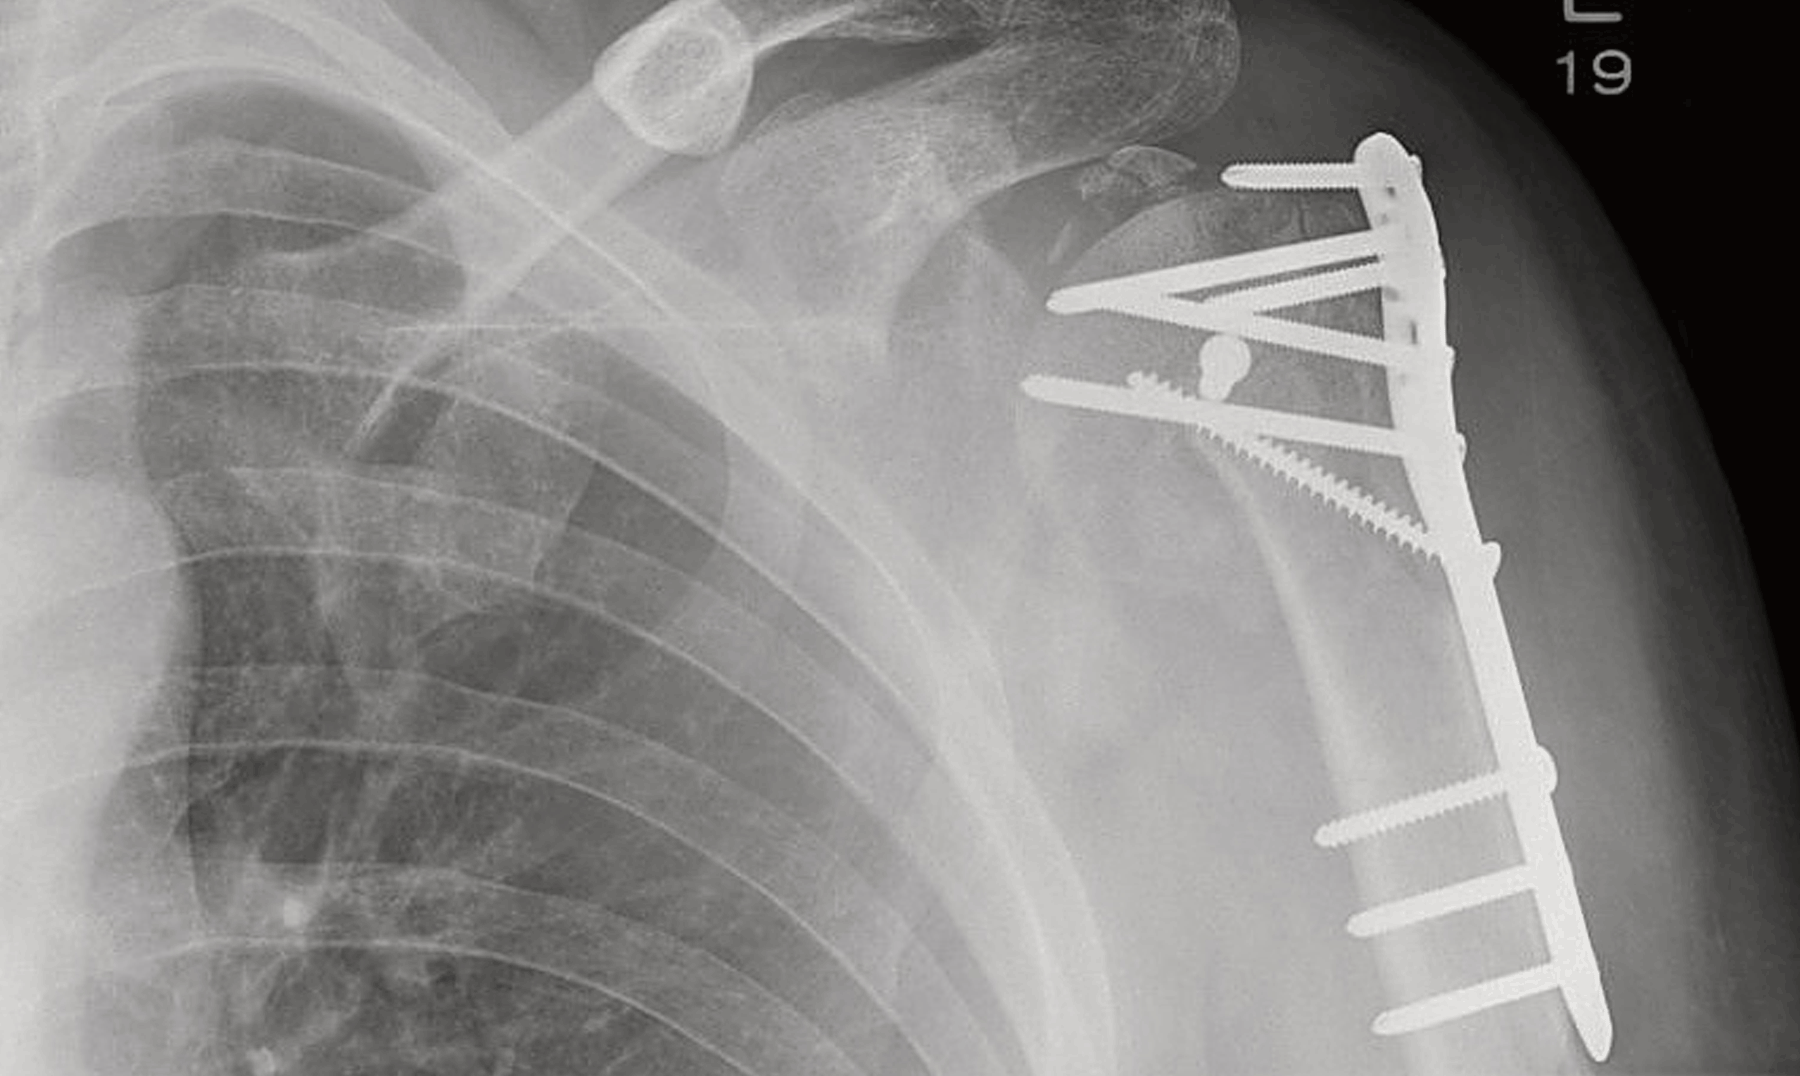

Metallisten luurikkojen korjaukseen käytettyjen osien ja ruuvien hyvä puoli on niiden hinta ja yksinkertaisuus, mutta ne pitää poistaa luun parannuttua. Tämä tarkoittaa potilaalle toista, ikävää leikkausta kaikkine harmeineen. Biologisesti luussa hajoavat polymeerikappaleet puolestaan ovat kalliimpia ja niiden asentaminen on yleensä työläämpää sekä vaatii enemmän ainetta luun sisälle ja ympärille. Niistä tulee myäs helpommin tulehduksia.